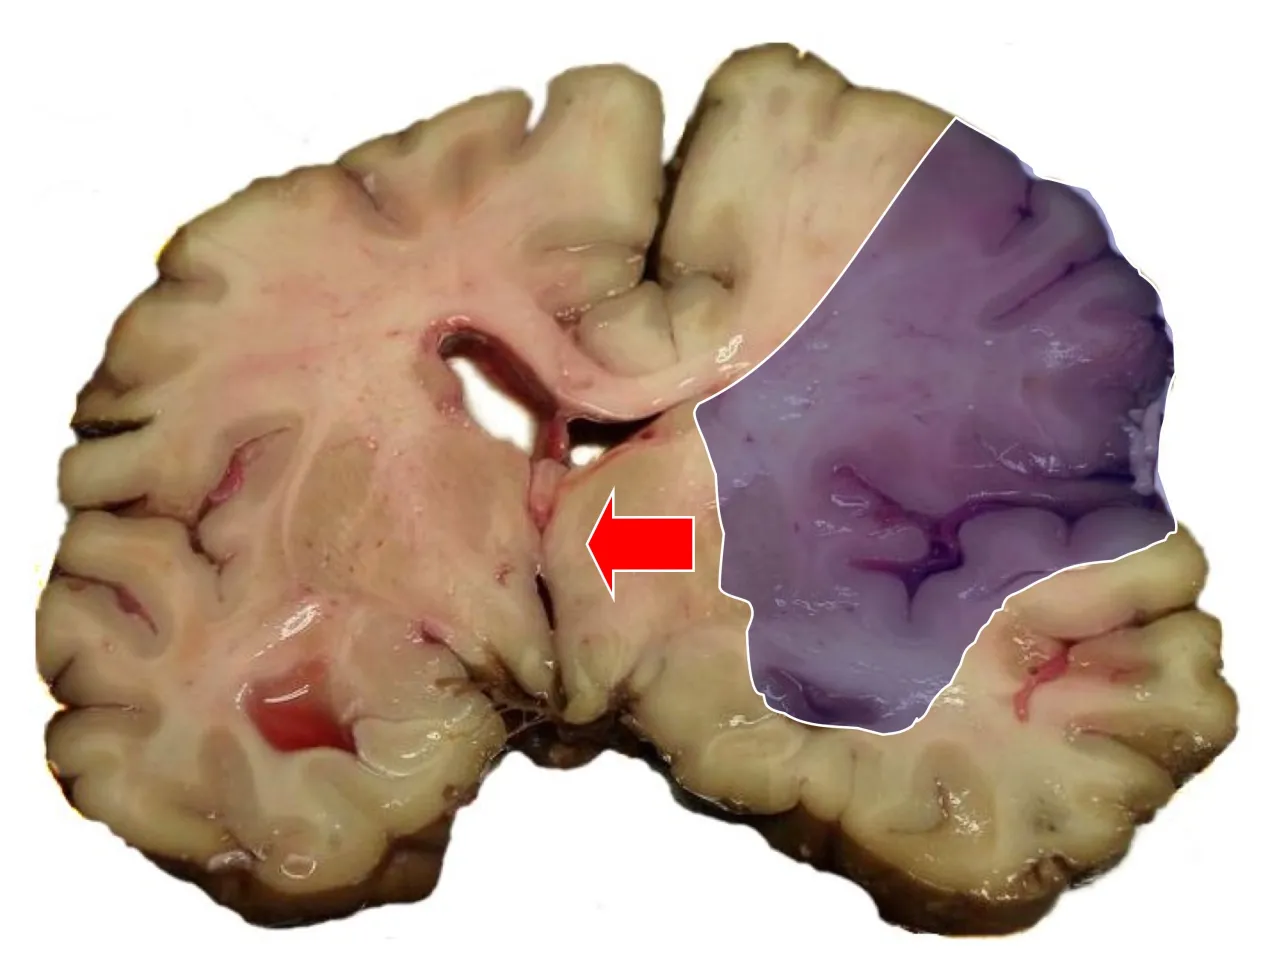

Kiedy mówimy o udarze, musimy pamiętać, że nie każdy udar jest identyczny, a to ma fundamentalne znaczenie dla rokowań. Wyróżniamy dwa główne typy: udar niedokrwienny, który stanowi około 85-87% wszystkich przypadków, oraz udar krwotoczny, odpowiadający za pozostałe około 15%. Udar niedokrwienny jest spowodowany zablokowaniem naczynia krwionośnego w mózgu, co prowadzi do niedotlenienia. Jego śmiertelność wynosi około 20%, a co cieszy, około 1/4 pacjentów po udarze niedokrwiennym wraca do pełnej aktywności. Z kolei udar krwotoczny, potocznie zwany wylewem, jest znacznie groźniejszy. Polega on na pęknięciu naczynia krwionośnego i wylewie krwi do mózgu. W jego przypadku śmiertelność sięga aż 50%, a połowa pacjentów umiera w ciągu pierwszych dwóch dni, szczególnie jeśli wylew dotyczy pnia mózgu, który kontroluje podstawowe funkcje życiowe. Ta drastyczna różnica w rokowaniach pokazuje, dlaczego tak ważne jest szybkie zdiagnozowanie typu udaru i wdrożenie odpowiedniego leczenia.

Lokalizacja i wielkość uszkodzenia mózgu mają bezpośredni i fundamentalny wpływ na rokowania. Mózg jest niezwykle złożonym organem, a różne jego obszary odpowiadają za odmienne funkcje. Udar obejmujący kluczowe obszary mózgu odpowiedzialne za funkcje życiowe, takie jak pień mózgu (szczególnie w udarze krwotocznym), ma znacznie gorsze prognozy, ponieważ uszkodzenie tych struktur może prowadzić do niewydolności oddechowej czy krążeniowej. Z kolei rozległość uszkodzenia decyduje o zakresie deficytów neurologicznych im większy obszar mózgu został dotknięty, tym poważniejsze mogą być konsekwencje, takie jak niedowłady, afazja (problemy z mową) czy zaburzenia poznawcze. To właśnie od tej "mapy zniszczeń" zależy potencjał do odzyskania sprawności i zakres rehabilitacji.